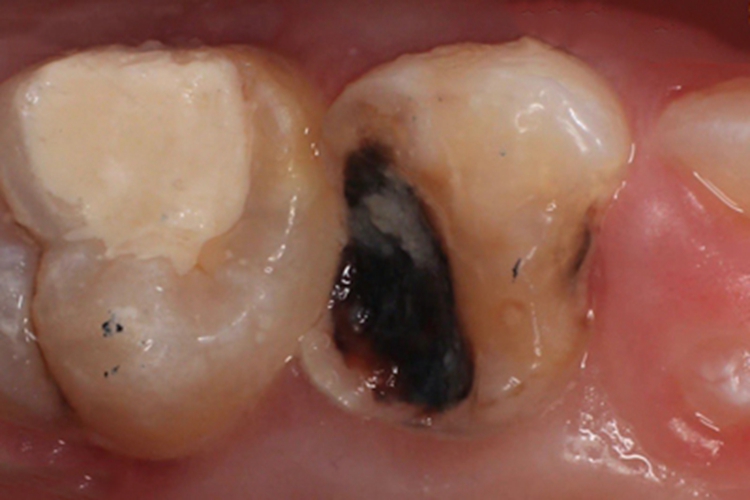

年轻恒牙龋黑斑图

对于开放性龋洞、多发性龋齿或猖獗龋,必须很快、粗略地去除腐质,用丁香油氧化锌糊剂暂封龋洞或玻璃离子充填,减少食物滞留,控制龋损进展,促进修复性牙本质形成,争取治疗时间。

对恒牙龋损要积极治疗,防止龋损扩大。